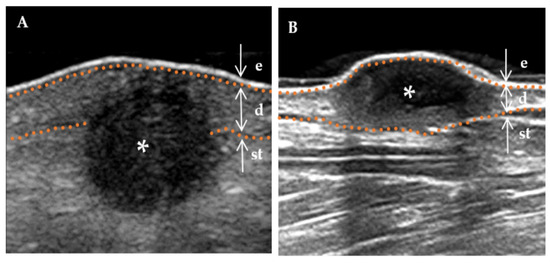

Figure 7.

Typical high-risk DF and low-risk DF. * Indicates the precise location of the lesion on the ultrasound image. The skin layers are indicated by dotted orange lines, with arrows indicating a hyperechoic epidermis (e), an isoechoic dermis (d), and a subcutaneous tissue (st). (A) A 32-year-old female presenting with a hemosiderin DF measuring 5.5 × 3.2 mm, exhibiting a hypoechoic area with a clear boundary and regular shape, predominantly located within the dermis. (B) A 36-year-old male patient presenting with a hemosiderin DF on the face, with a mixed echo zone of 15.1 × 6.5 mm. The lesion exhibits an unclear boundary and irregular shape, extending beyond the dermis into the subcutaneous tissue layer.